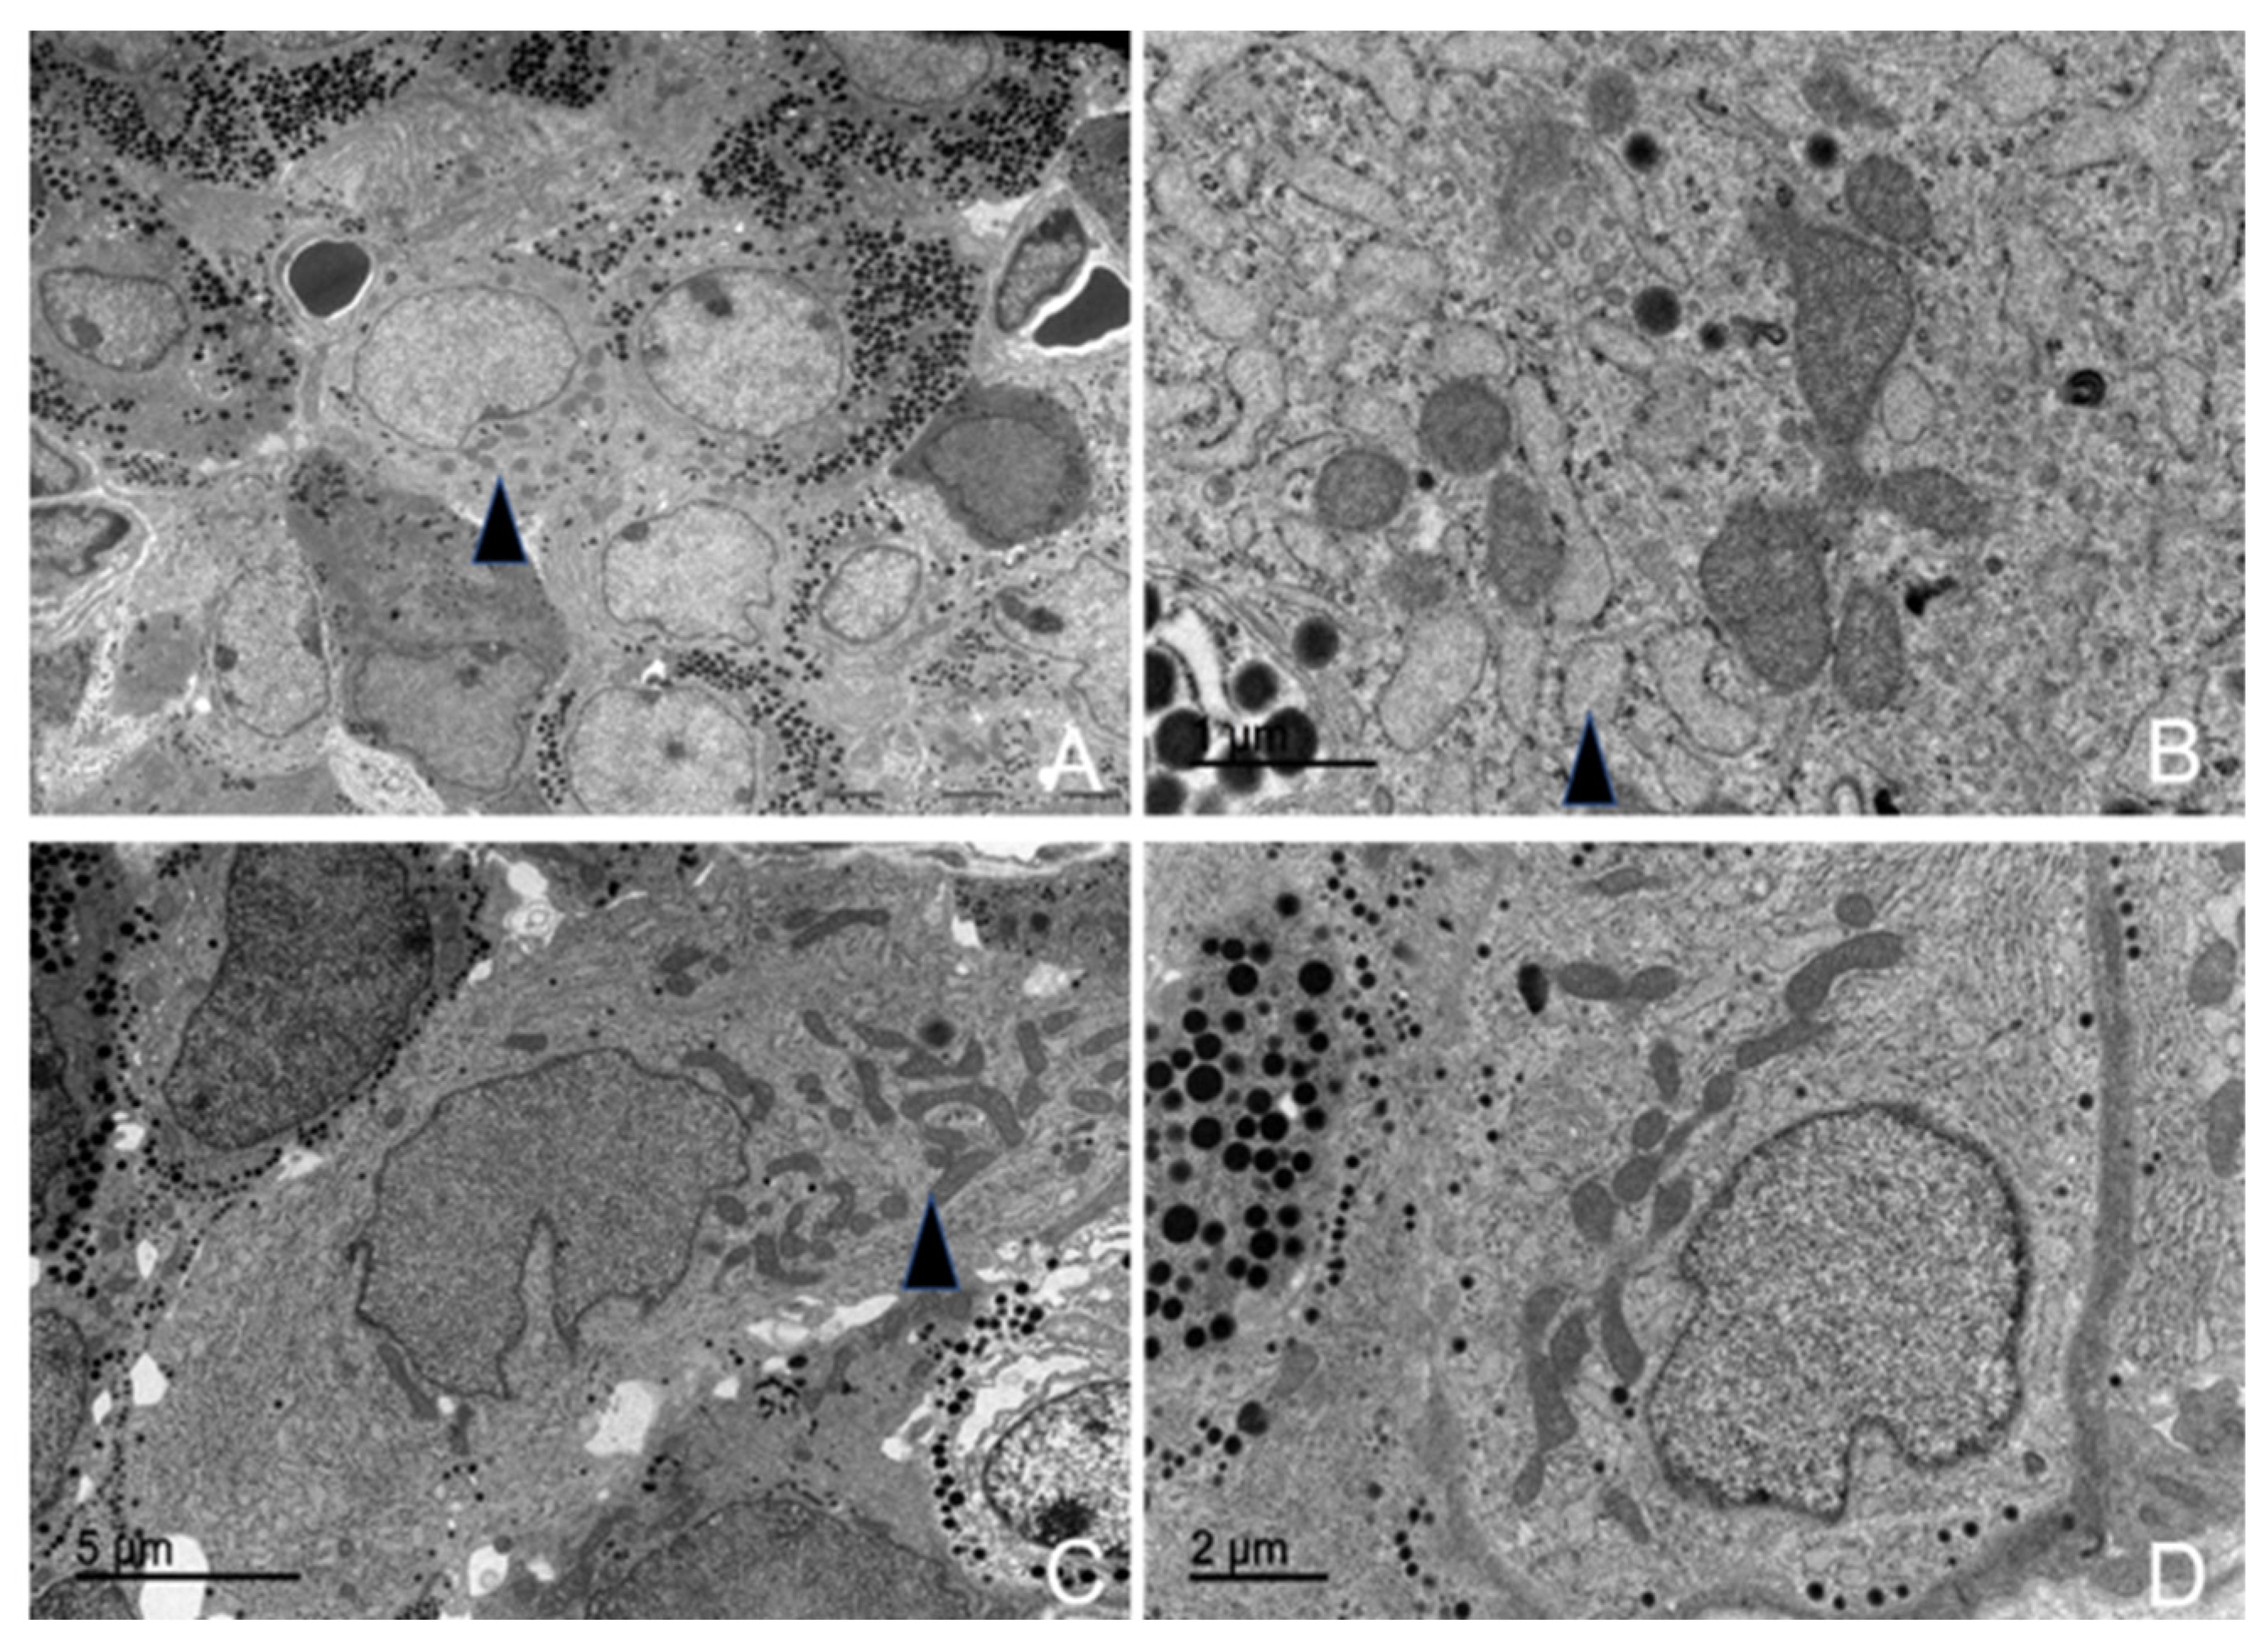

3.5.5. Thyrotrophs (TSH-Producing Cells)

3.5.6. Melanotrophs (MSH-Producing Cells)

3.5.7. Follicular Cells

3.5.8. Capsular Cells